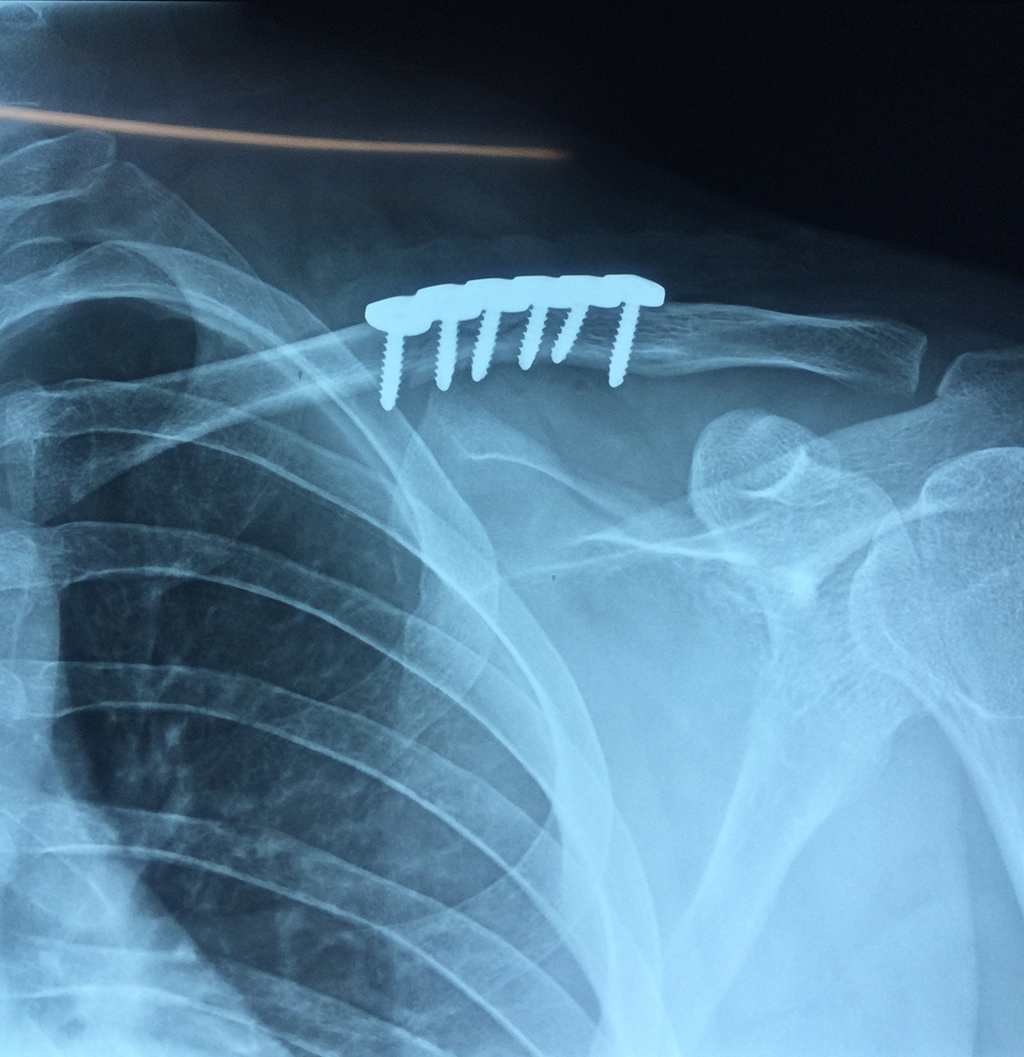

Cirugías de Codo - Clavícula

La clavícula es un hueso largo, con forma de "S" itálica, situado en la parte anterosuperior del tórax. Junto con la escápula forman la cintura escapular. Se puede palpar por toda su longitud y se extiende del esternón al acromion de la escápula, siguiendo una dirección oblicua lateral y posterior.